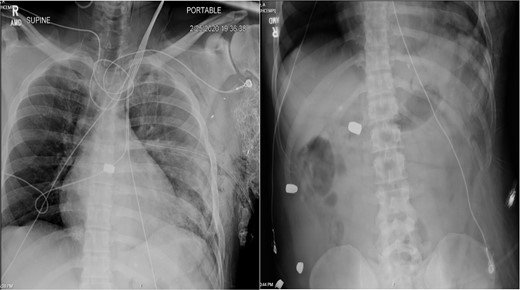

A 36-year-old male presented with multiple thoracoabdominal GSW (4 GSW in the left axilla, 2 GSW right flank). The patient had decreased breath sounds on the left. Initial vital signs were heart rate 141, blood pressure 70/40, respiratory rate 22, saturation 92% on 15 L non-rebreather, GCS 14. The patient underwent a left thoracostomy tube with 1000 mL initial output and a 9F left femoral central line was placed. The patient was initially resuscitated with 2 units PRBC, 2 units FFP with no improvement in vital signs. A plain film X-ray in the trauma bay revealed multiple thoracoabdominal bullets (Fig. 3). The patient went emergently to the OR for hemorrhage control.

Plain film X-ray obtained in the trauma bay demonstrating multiple bullets overlying the cardiac silhouette and right abdomen.

Case 2 involved a hemodynamically unstable patient with multiple thoracoabdominal GSWs. The surgical team identified six GSWs and five retained bullets. The patient’s instability precluded CT imaging. A cardiac injury was suspected due to a bullet overlying the cardiac silhouette and significant chest tube output. Thoracotomy confirmed a cardiac injury with tamponade, necessitating immediate repair. The bullet trajectory suggested it passed through the heart and diaphragm into the abdomen. TEE revealed no intracardiac shunting, valve insufficiency, or bullet. The bullet injured the left ventricle and embolized to the aortic root, becoming symptomatic on hospital Day 7. A CT scan suggested an intravascular bullet near the aortic valve, confirmed by TEE showing severe aortic insufficiency. The patient required four operations for definitive management. This case underscores the risks of conservative management and the need for thorough evaluation in unstable patients.